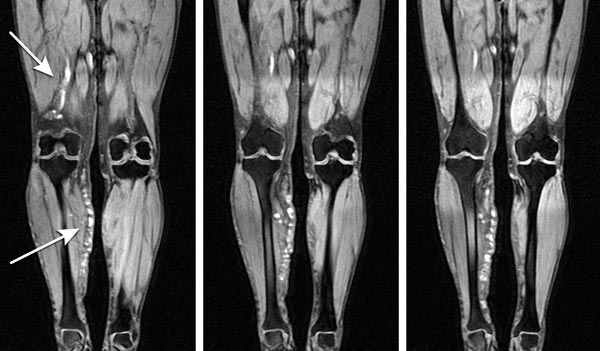

В настоящее время диагностика варикозной болезни нижних конечностей включает в себя различные инструментальные методы. Главная цель инструментальных методов диагностики варикозной болезни - топическая характеристика нарушений флебогемодинамики, рентгеноанатомическая оценка состояния глубокой венозной системы и путей коллатерального кровотока.

сравнительный анализ возможностей ультразву-ковой и рентгеноконтрастной флебографии в диагностике клапанной недостаточности бедренной вены (БВ), глубокой вены бедра (ГВБ) и подколенной вены (ПВ) у пациентов с варикозной болезнью.

нами проведен анализ результатов обследования и оперативного лечения 115 пациентов с различными формами варикозной болезни в возрасте от 18 до 68 лет, из них мужчин было 21 (18%), женщин - 94 (82%). Всем пациентам было выполнено триплексное ультразвуковое сканирование (УЗФГ) и рентгеноконтрастная флебография (РКФГ). Проба Вальсальвы больными при ультразвуковом и рентгеноконтрастном обследовании выполнялась стандартно: пациенты максимально натуживались в течение 0,5-1 секунды и удерживали внутрибрюшное давление в течение 10 секунд. Для контрастирования вен использовали 76% раствор триомбраста.

полная недостаточность клапанов БВ при РКФГ выявлена у 43 (37,4%) пациентов, аналогичный результат получен и при триплексном сканировании. Частичная недостаточность клапанов БВ при рентгеноконтрастной флебографии выявлена у 30 (26,1%) больных. При УЗФГ частичная недостаточность клапанов БВ диагностирована у 24 (20,9%) пациентов, у 6 (5,2%) результат был сомнительный. При полной клапанной недоста-точности рефлюкс диагностировался по всей бедренной вене, при частичной до границы верхней и средней трети бедра.

При РКФГ недостаточность клапанов ПВ выявлена у 12 (10,4%) пациентов, аналогичные результаты получены и при УЗФГ. Состоятельность клапанов ПВ при РКФГ отмечена у 103 (89,6%) пациентов, при УЗФГ у 89 (77,4%), сомнительный результат был у 26 (22,6%). Применение РКФГ также позволило диагностировать ретроградное заполнение ПВ из глубокой вены бедра при состоятельности клапанов БВ у 11 (9,5%) из 115 пациентов. Ультразвуковые методики в этом вопросе пока не могут составить конкуренции рентгеноконтрастной флебографии, так как из-за большой мышечной массы бедра редко удается визуализировать глубокую вену бедра дистальнее 3-4 см от её устья.

современные ультразвуковые методы играют ведущую роль в диагностике и определения объема операции у больных с несостоятельностью клапанов бедренно-подколенного сегмента при варикозной болезни. Рентгеноконтрастная флебография должна использоваться при сомнительных результатах, при патологии глубокой вены бедра, а также для определения метода коррекции несостоятельности клапанов.